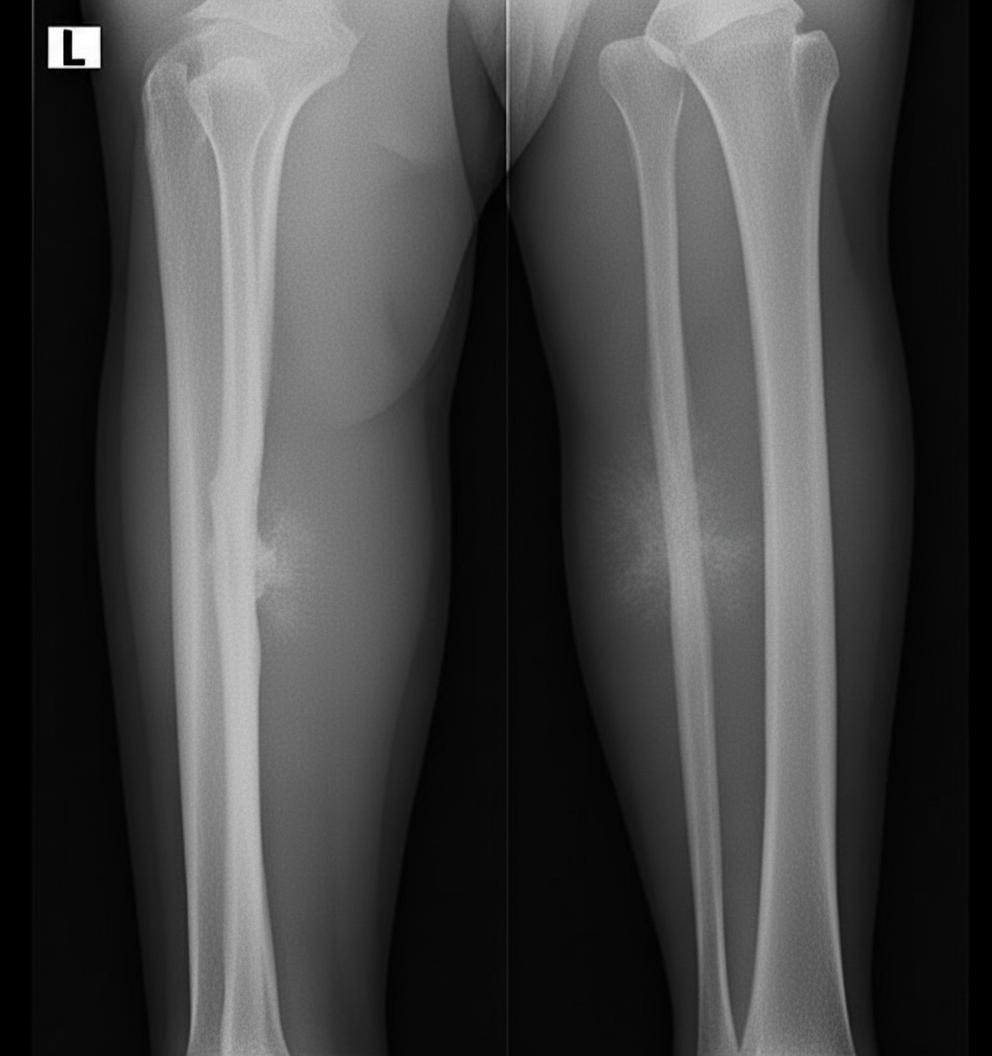

Which of the following is the most probable diagnosis given the provided X-ray?

Explanation: ***Fluorosis*** - **Osteosclerosis** with increased bone density and **calcification of ligaments and tendons** are pathognomonic X-ray features of skeletal fluorosis. - **Calcified interosseous membranes** between radius-ulna and tibia-fibula create characteristic "bamboo spine" appearance in advanced cases. *Caffey's disease* - Presents with **cortical hyperostosis** and **periosteal new bone formation** primarily affecting long bones in infants. - X-rays show **thickened cortices** with **soft tissue swelling**, not the diffuse sclerosis seen in fluorosis. *Rickets* - Characterized by **osteopenia**, **delayed ossification**, and **metaphyseal changes** like cupping and fraying. - X-rays show **bowing deformities**, **coxa vara**, and **widened growth plates**, opposite to the sclerotic changes in fluorosis. *Scurvy* - Shows **osteopenia** with **cortical thinning** and **metaphyseal corner fractures** (Pelkan's sign). - **Wimberger's ring** around metaphyses and **ground glass osteopenia** are typical, contrasting with fluorosis's increased density.